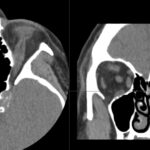

- Radiology Cases: Images with a to-the-point discussion highlighting the specific diagnostic criteria.

- Radiology Case of the Day Collection: Aunt-Minnie Board Cases for Rapid Review.

Latest Radiology Cases